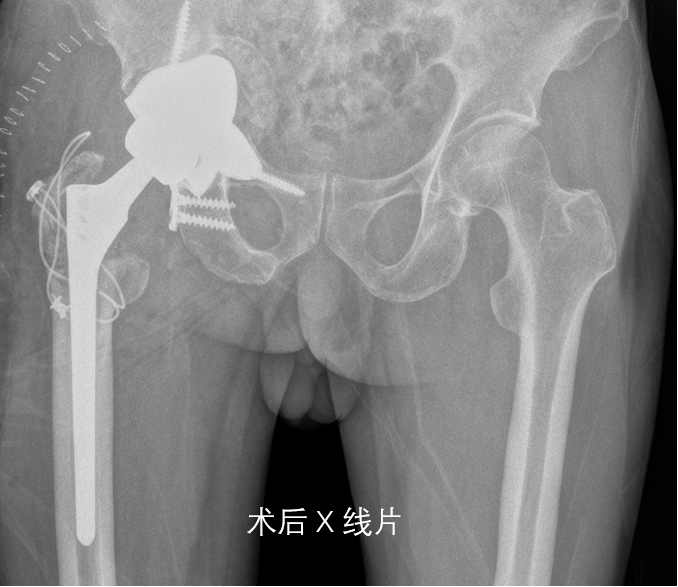

在进行详细的术前评估后,我院骨科共同讨论制定了一套个性化手术方案,即通过3D打印技术,骨盆模型并根据缺损情况定制一体式髋臼假体。经过周密的术前准备后,黄老先生接受了翻修手术,术中林俊主任团队按照术前规划稳步实施手术:暴露、清创、脱位、取股骨假体、取髋臼假体、冲洗、放置假体……经过近7个小时的连续作战,在麻醉手术科的全力配合下手术终于圆满完成。